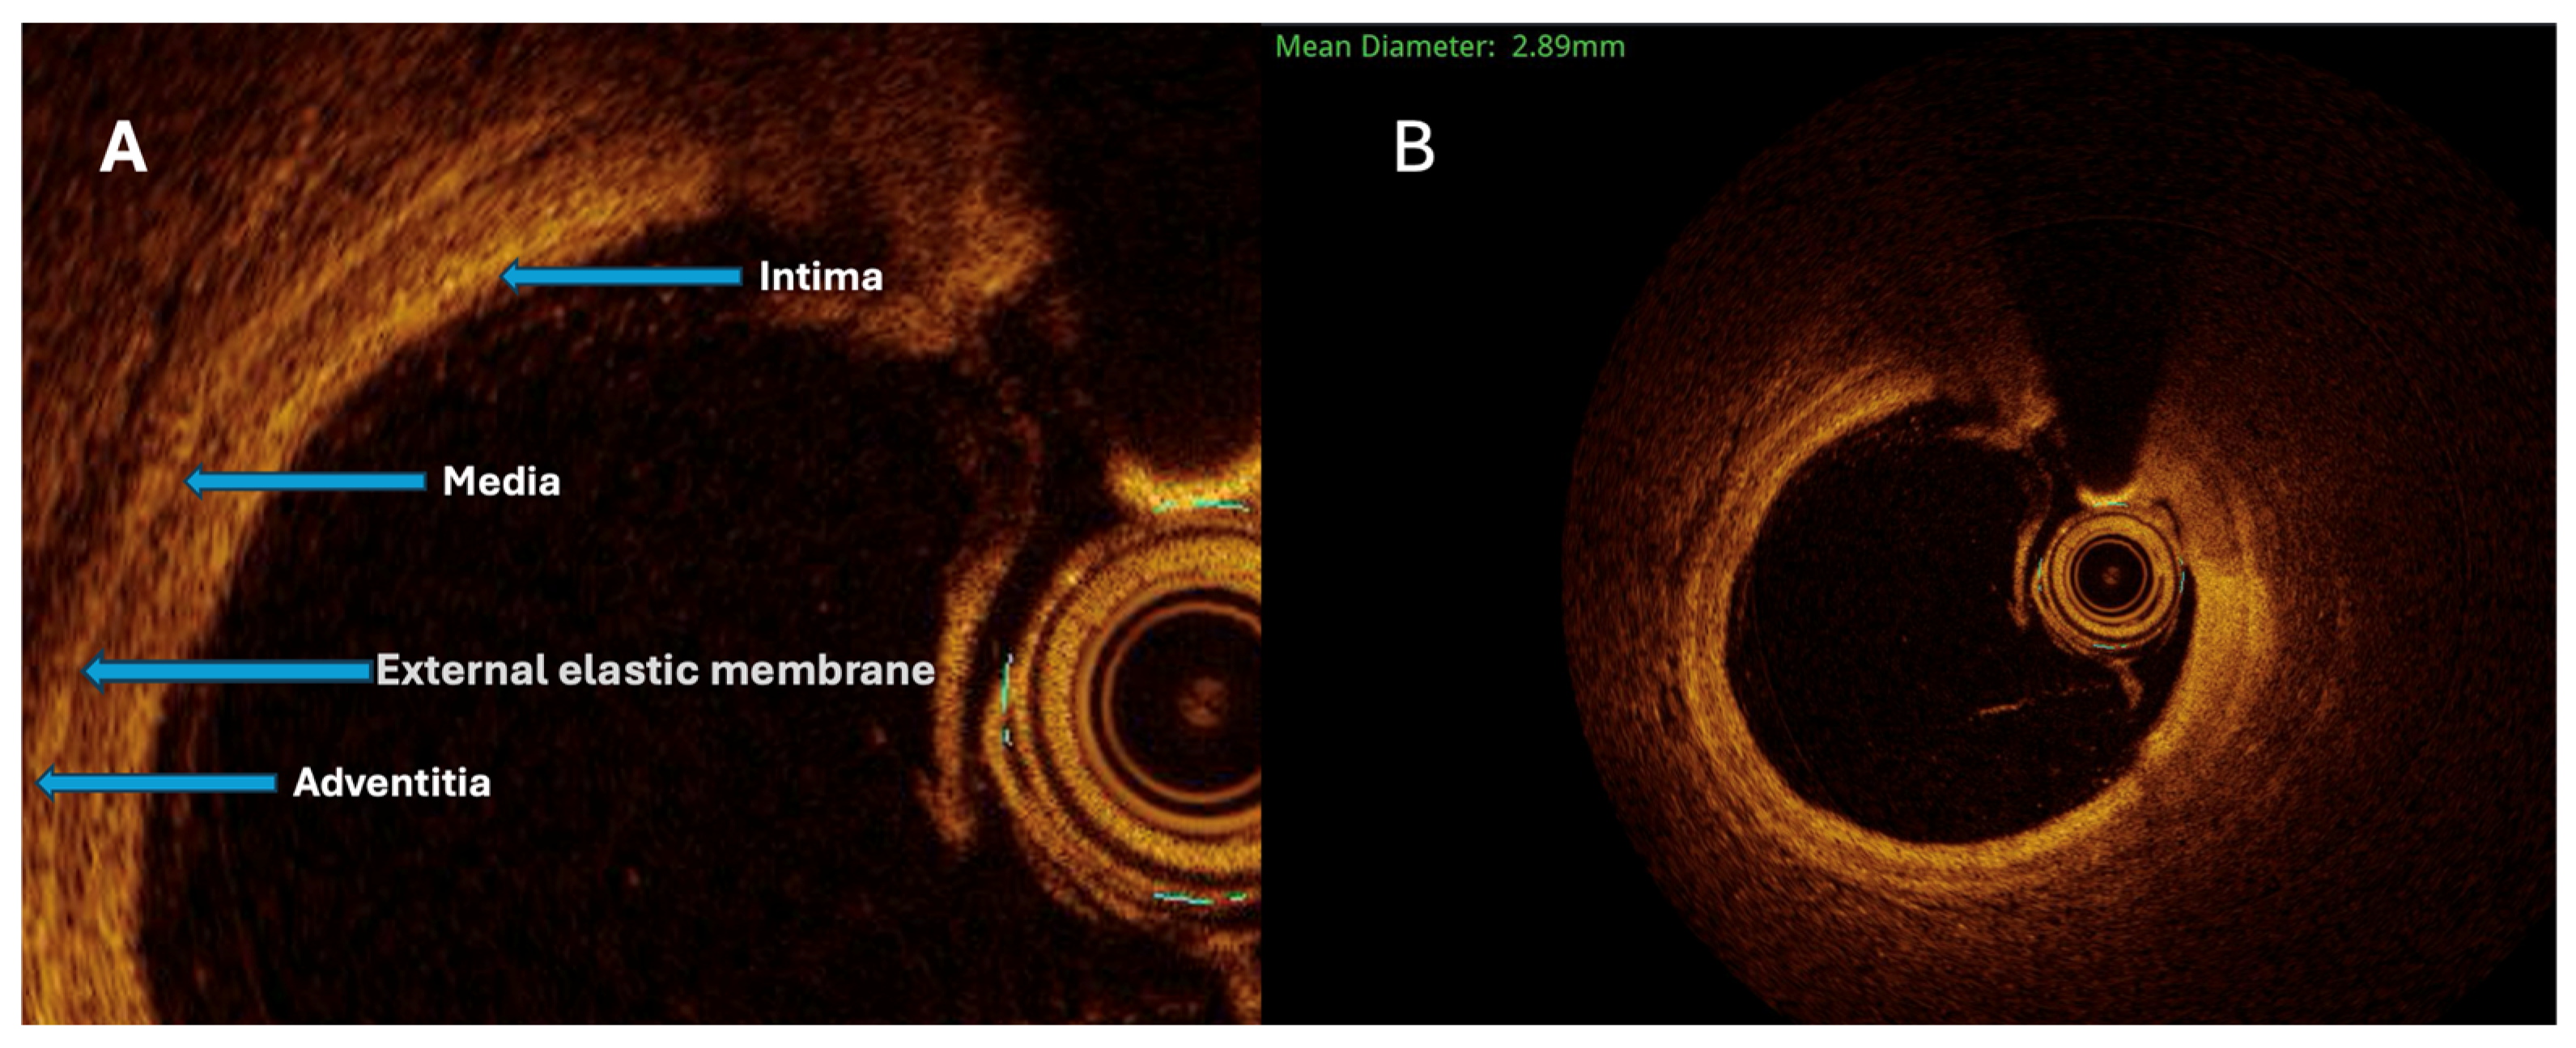

The maximal aneurysm diameter (right, within the aneurysmal segment) is measured perpendicularly across the lumen at the point of most significant dilation. The reference diameter (left) is measured perpendicularly across the lumen of the adjacent, non-dilated (normal) segment of the same vessel, proximal to the aneurysm. The aneurysmal ratio is calculated as the maximal aneurysm diameter divided by the reference diameter; values ≥1.5 indicate aneurysmal remodeling according to standard interventional definitions. The normal coronary vessel, with all its layers, is presented in

Figure 3.